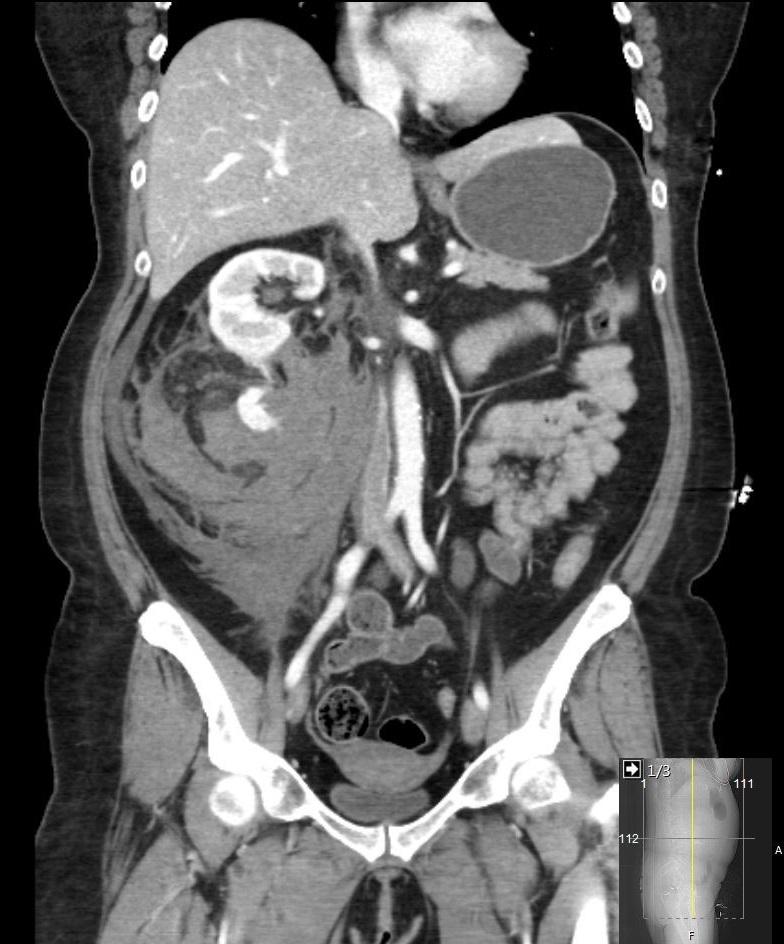

Een 55-jarige vrouw komt op de SEH vanwege acuut ontstane pijn in de rechter flank en een neiging tot flauwvallen. Bij lichamelijk onderzoek is zij bleek en hemodynamisch instabiel, en is in de rechter flank een zwelling voelbaar. Zij geeft daarbij slagpijn in de rechter nierloge aan. Welke afwijking ziet u op de CT-scan van het abdomen?

Wat is uw diagnose?